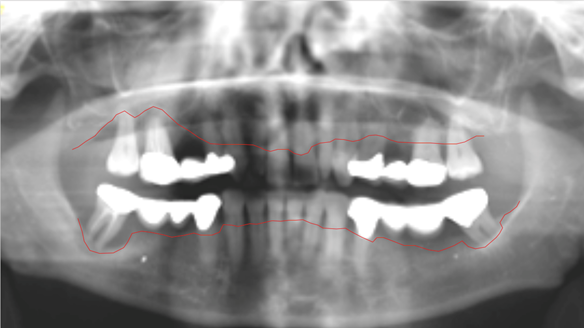

This newsletter describes in step by step detail Angela's transition through immediate partial dentures to crown supported definitive metal based dentures.

This 58 year old woman was referred to me by her general dental practitoner for treatment.

- Generalised Periodontitis; Stage 4, Grade C, Currently Unstable. Risk Factors: Type 1 diabetes. 16, 17 - hopeless prognosis. 14, 24, 26, 27, 34, 37, 44 - guarded prognosis

The clinical situation and treatment process is shown in detail below with photographs. I (Finlay Sutton) provided the clinical work and Rowan Garstang provided the technical work.